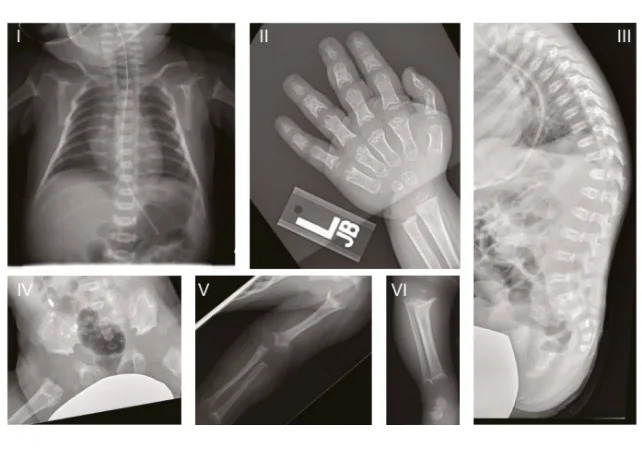

Researchers at Helmholtz Munich linked mutations in the GPX4 gene to progressive inflammation and neuronal loss in mouse models and in human neurons grown from patient skin cells. The human disorder studied, Sedaghatian-type spondylometaphyseal dysplasia (SSMD), is an ultra-rare condition first described in 1980 that causes severe brain and skeletal abnormalities and, in many cases, early infant death.